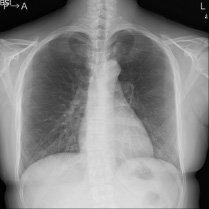

一般撮影の撮影画像

胸とお腹の輪切り画像

3D画像